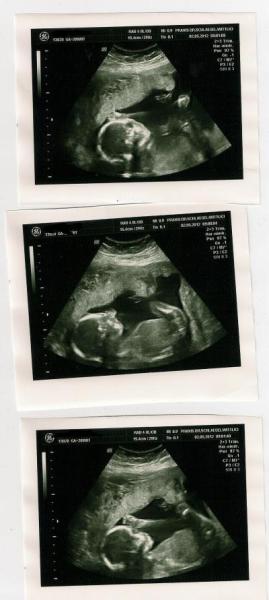

Hallo zusammen, jetzt komm ich auch mal von meiner VU am Mittwoch zu berichten. Bin heute 20+2 und hab die Hälfte geschafft, jetzt beginnen die anstrengenden Monate ;-) Seit ner guten Woche meldet sich der Zwerg auch mal trotz wieder VWP. So 100% outen wollte er sich immer noch nicht, aber ich war ja nach meinem Treppensturz im KH und da meinte die Ärztin es sei ein Mädchen. Und ich find auch es sieht aus wie bei Charlotte. Aber egal, Zwergi ist gesund und munter, alles dran und zeitgerecht entwickelt. Ist jetzt etwa 23cm groß und wiegt ca. 350g. In 2 Wochen kommt zum ersten Mal die Hebamme, die auch schon bei Charlotte als Nachsorgehebi da war und in 4 Wochen darf ich zum Zuckertest. Anbei noch 3 Bildchen von unserer hoffentlich Prinzessin! LG Anne